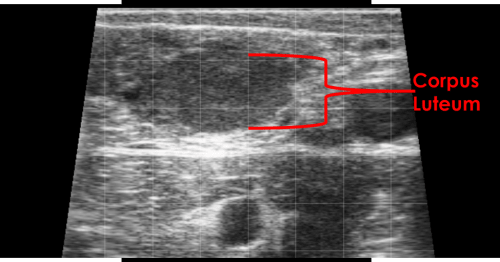

Corpus Luteum

The corpus luteum appears as a defined area of hypoechoic tissue within the ovarian stroma.